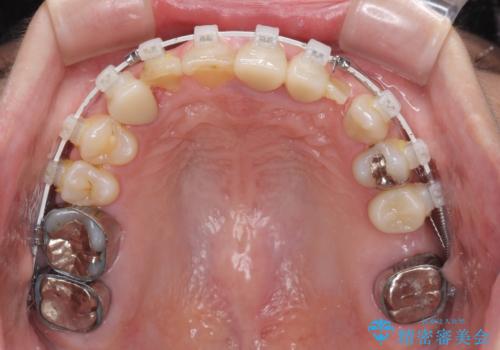

咬み合わせ改善のため、前歯の過剰歯を抜去し、ワイヤー矯正にて歯列と咬み合わせることとしました。

左上の奥歯のブリッジや前歯のセラミッククラウンはいったん除去し、矯正治療後に補綴治療を行うこととしました。

また、右下の抜歯が必要な奥歯は、矯正治療の途中でインプラントを埋入し、矯正治療後に上顎と合わせて補綴治療を行うこととしました。

上下非接触の咬み合わせは、舌突出癖によるところが大きく、トレーニングを行いながら治療を進めていきました。

なかなか突出癖が改善できず、過剰歯を抜歯したスペースを閉じるまでに時間がかかりました。

舌突出癖の改善は、治療期間や仕上がりに大きな影響を与えるため、しっかりとトレーニングすることが大切です。